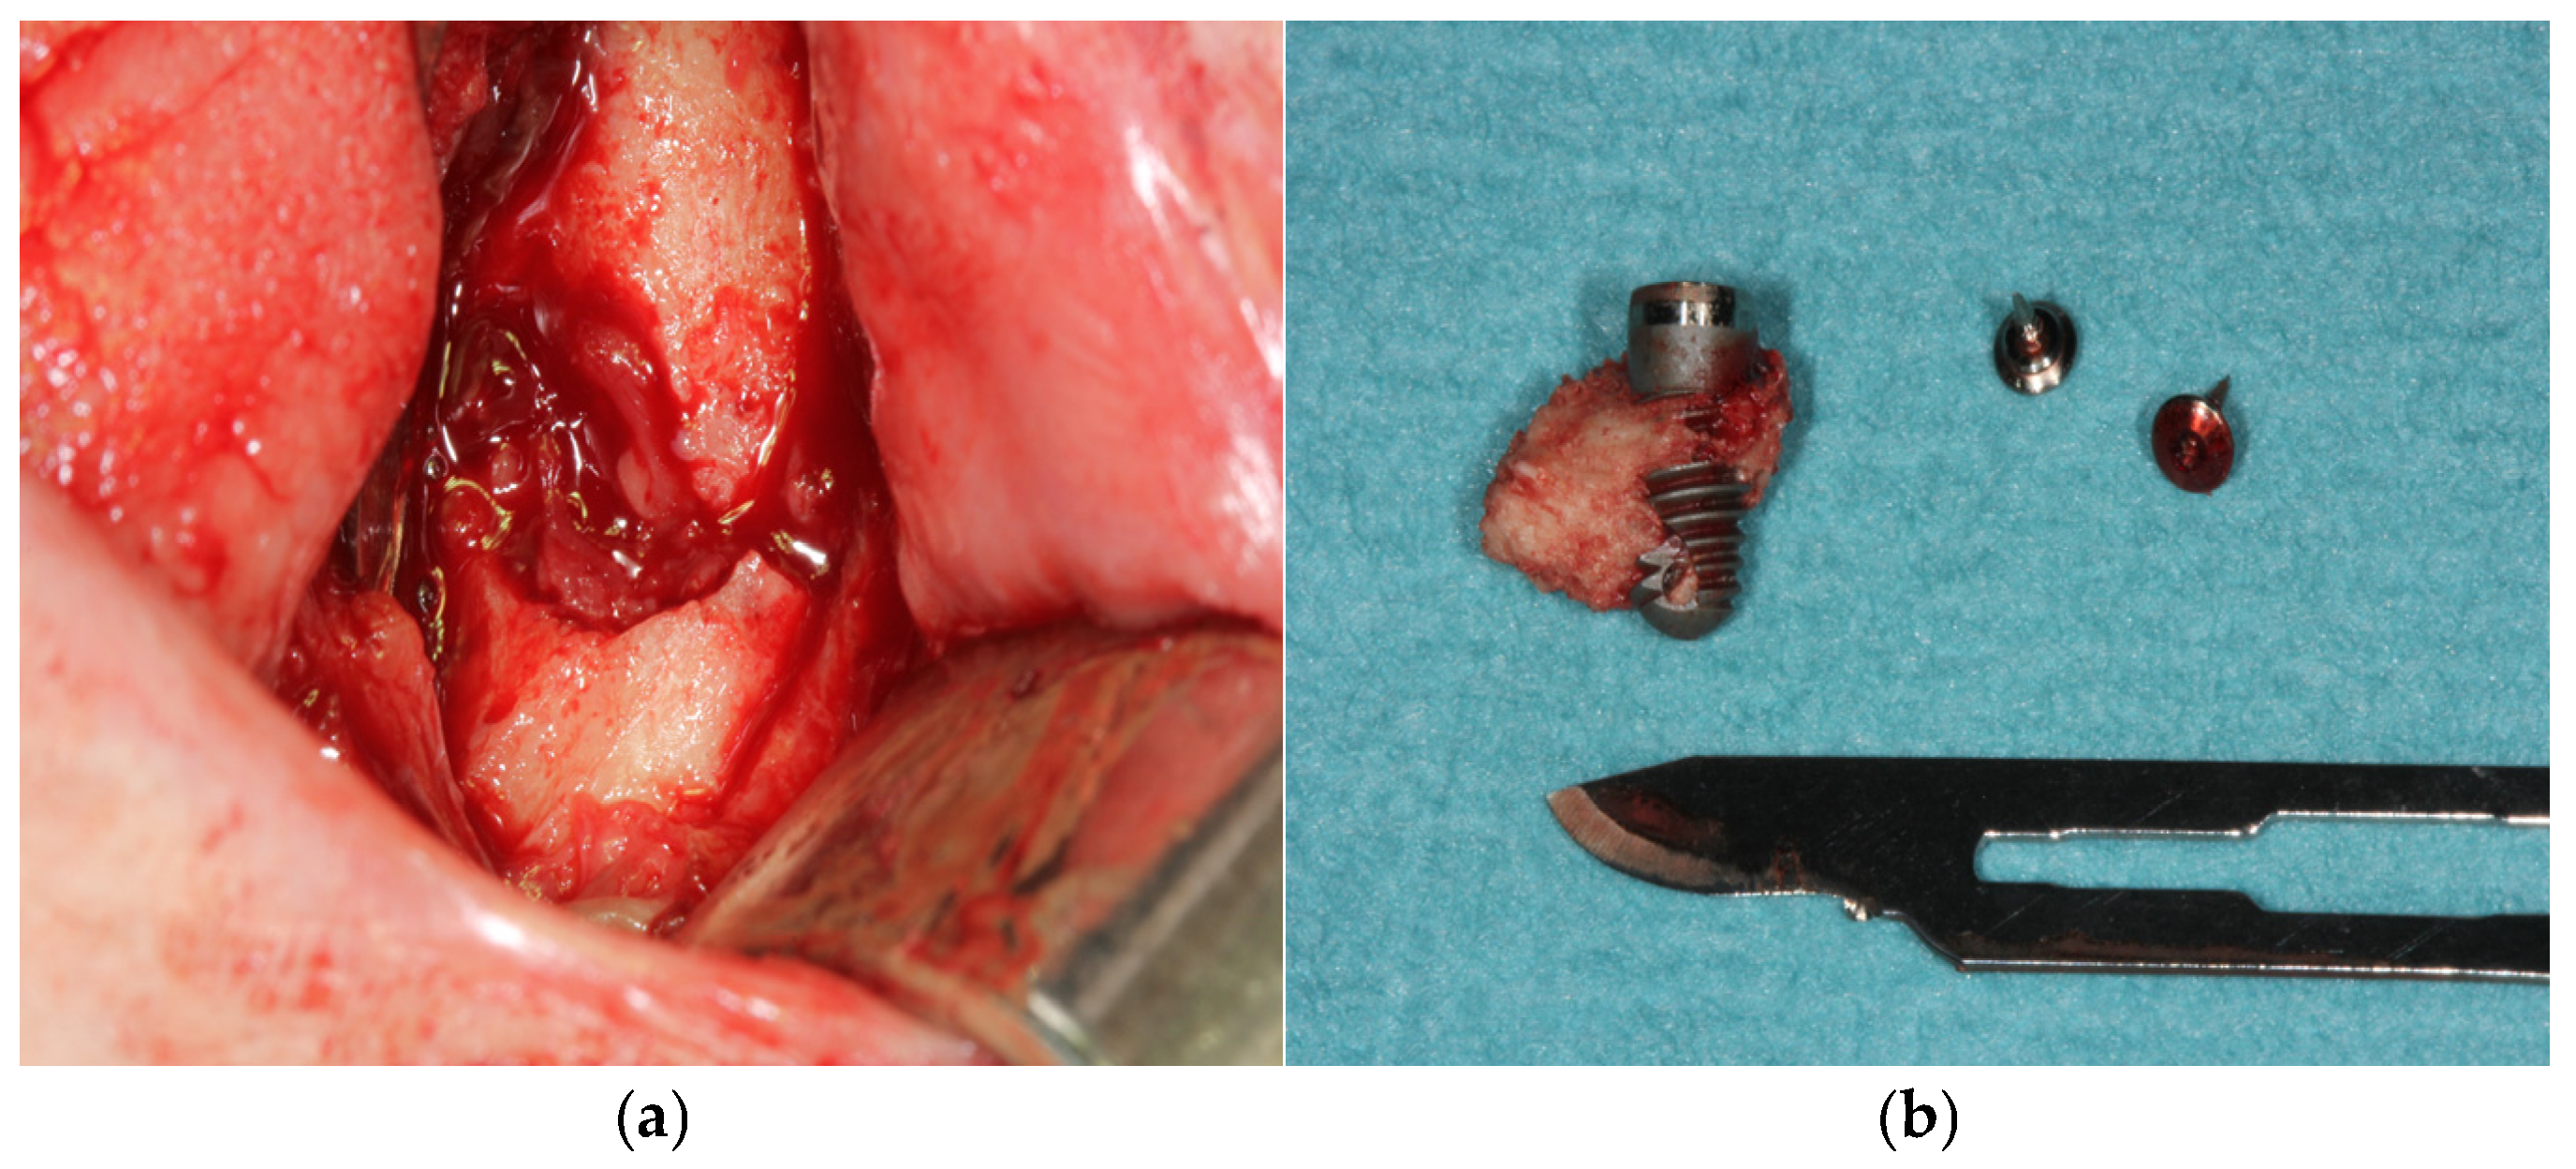

3.1. Case 1

3.2. Case 2

| Implants removal | Yes | 2 (33.33%) |